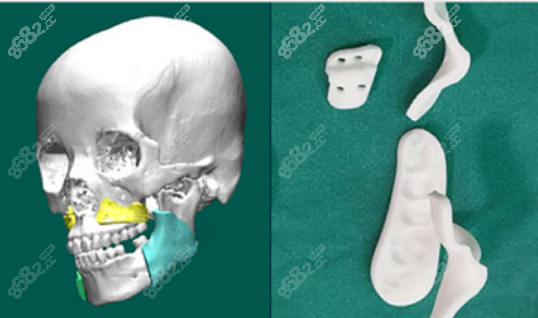

优势1:广州广大医院双鄂手术做的是3D导板双鄂手术,也就是双鄂导航手术,能够提前预知术后样子。

优势2:做的3D打印导板能够更准的定位截骨,包括定位截骨线、截骨范围、去骨量等,不会出现截骨量多的情况,做双鄂手术3年、5年或10年后不会出现脸下垮。

优势5:广大医院双鄂手术中有3D打印咬合板指导上下颌骨移动方向和距离,精细到0.01mm,术后和术前看到的样子一致。